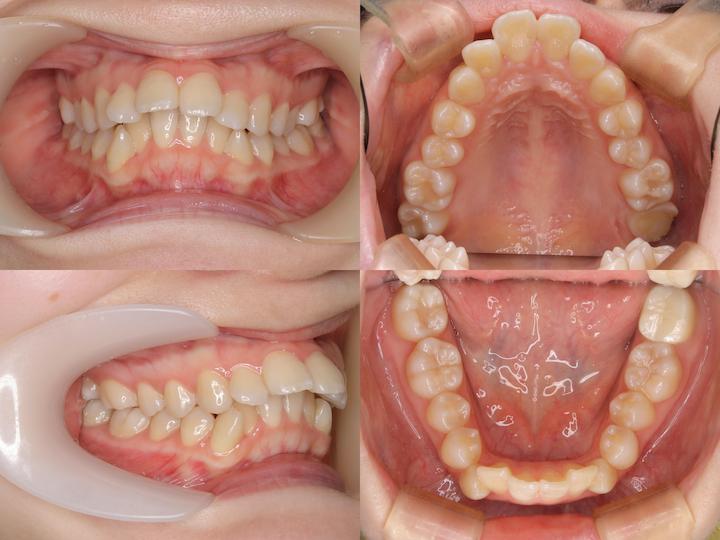

初診時年齢33歳5ヶ月の患者様です。口の閉じ辛さと歯の重なりを主訴にご来院されました。

上下左右4番を抜歯してアンカースクリューで上顎6番を遠心移動しながら前歯を後方に牽引しました。

さらに上顎大臼歯を圧下(上方向に移動)して下顎骨の前上方への回転を促しました。